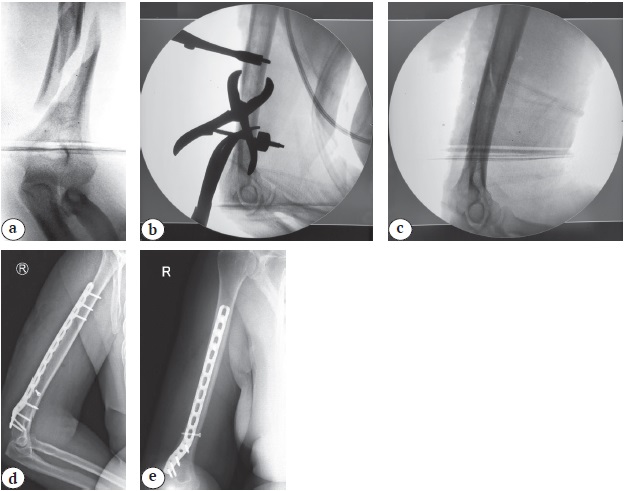

Хомуты-стяжки изготовлены из рентгенопрозрачного материала, что наделяет их уникальными свойствами по сравнению с любым другим металлическим хирургическим инструментом. Нередко при рентгеноскопии во время операции металлические костодержатели и зажимы закрывают важные участки, усложняя контроль качества репозиции (рис. 5 a, b). Пластиковые устройства не создают в этом отношении препятствий — во время операции они не мешают визуализировать кость на любом участке (рис. 5 c). Качество удержания отломков во время остеосинтеза подтверждается послеоперационными рентгенограммами (рис. 5 d, e).

Рис. 5. Интраоперационные и послеоперационные рентгенограммы:

a — до начала репозиции;

b — после наложения костодержателей и хомутов-стяжек;

c — после снятия металлических костодержателей (отломки удерживаются в правильном положении хомутами-стяжками);

d, e — после операции

Fig. 5. Intraoperative and postoperative X-rays:

a — before the start of the reposition;

b — after applying bone clamps and ty-raps;

c — after removal of metal bone clamps (fragments are held in the correct position by ty-raps);

d, e — postoperative X-rays